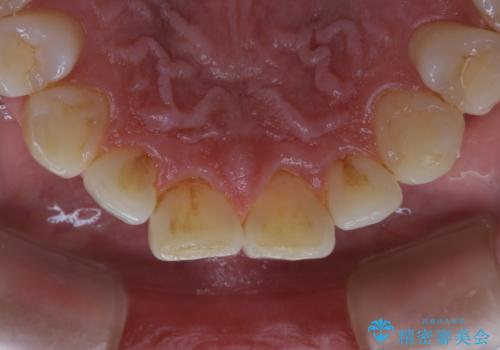

タバコによるヤニをPMTC(歯科医院での専門的クリーニング)で除去。